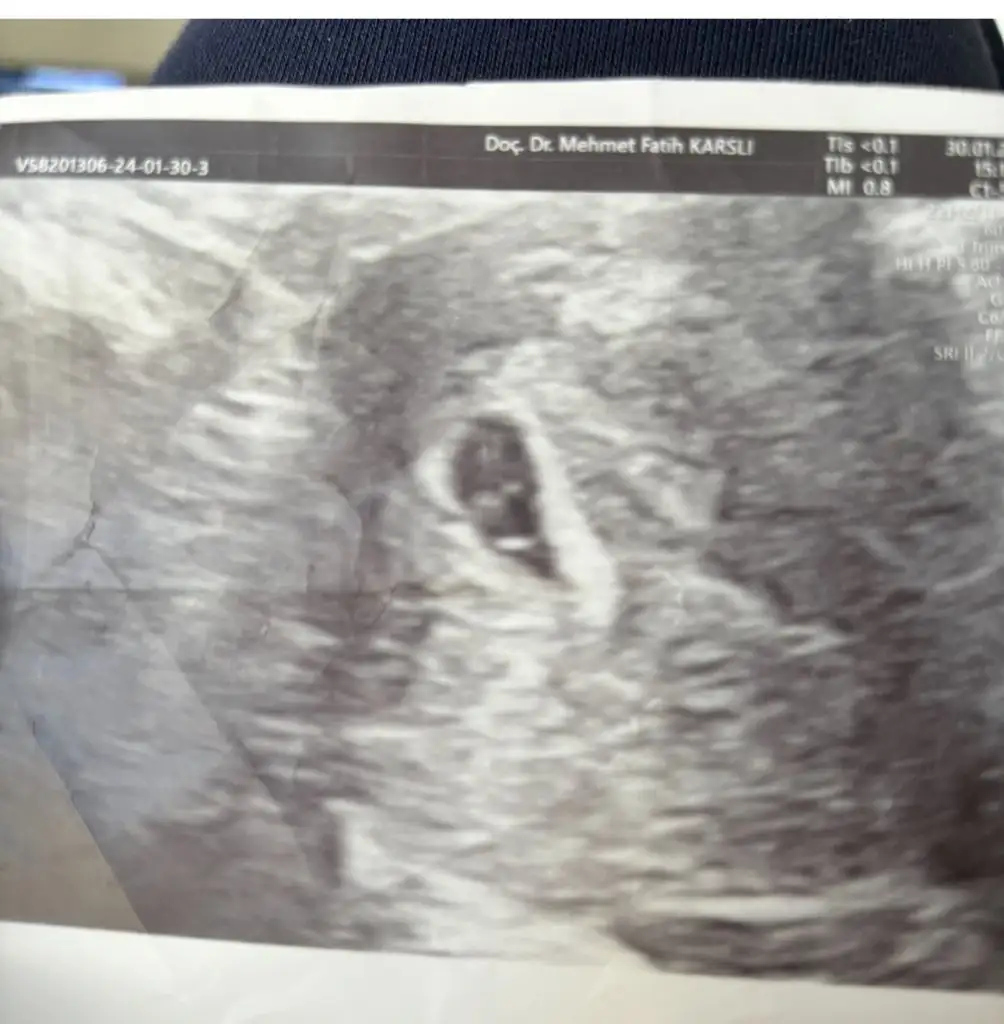

T Tali89 üstad sen bu işi nasıl yapıyorsun bi anlatCihazı bastırınca kese şekli değişiyor ama boyle goruntulerde var 5-6 hafta bi tanesinde yolk sac gorunmuyor ama fotografa basmamıs goruneni

Eki Görüntüle 3384379